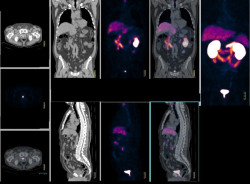

La alta carga de mutaciones tumorales predice la respuesta a la inmunoterapia en algunos cánceres, pero no en todos

Una alta tasa de mutaciones genéticas dentro de un tumor, conocida como carga de mutación tumoral alta (MTA), solo fue útil para predecir las respuestas clínicas a los inhibidores de puntos de control inmunitarios en un subconjunto de tipos de cáncer, según un nuevo estudio dirigido por investigadores de la Universidad de Centro Oncológico MD Anderson de Texas.